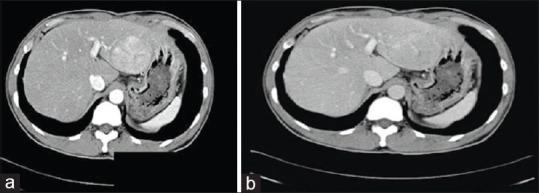

Hepatocellular carcinoma (HCC) is an epithelial tumor derived from hepatocytes; it accounts for 80% of all primary liver cancers and ranks globally as the fourth leading cause of cancer-related deaths. HCC treatment is a multidisciplinary and a multimodal task, with surgery in the form of liver resection and liver transplantation (LT) representing the only potentially curative modality. However, there are variable opinions and discussions about applying these surgical options and using other supporting treatments. This article is a narrative review that includes articles published from 1984 to 2013 located by searching scientific databases such as PubMed, SCOPUS, and Elsevier, with the main keyword of hepatocellular carcinoma in addition to other keywords such as liver transplantation, liver resection, transarterial chemoembolization, portal vein embolization, bridging therapy, and downstaging. In this review, we focus mainly on the surgical treatment options offered for HCC, in order to illustrate the current relevant data available in the literature to help in applying these surgical options and to use other supporting treatment modalities when appropriate.

肝细胞癌(HCC)是一种起源于肝细胞的上皮性肿瘤;它占所有原发性肝癌的80%,在全球范围内是癌症相关死亡的第四大主要原因。HCC治疗是一项多学科、多模式的任务,肝切除和肝移植(LT)形式的手术是唯一具有潜在治愈可能的治疗方式。然而,对于应用这些手术选择以及使用其他支持性治疗存在不同观点和讨论。本文是一篇叙述性综述,纳入了通过检索科学数据库(如PubMed、SCOPUS和Elsevier)找到的1984年至2013年发表的文章,主要关键词为肝细胞癌,此外还有肝移植、肝切除、经动脉化疗栓塞、门静脉栓塞、桥接治疗和降期等其他关键词。在本综述中,我们主要关注为HCC提供的手术治疗选择,以阐明文献中现有的相关数据,帮助应用这些手术选择并在适当的时候使用其他支持性治疗方式。